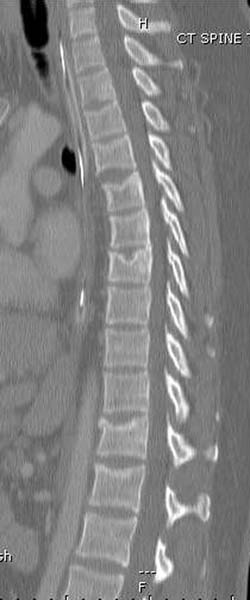

> Перелом позвоночника и боковую компрессию таза отнесли к стабильным

> переломам и не стали форсировать события до лучших времен...

> После спадения отека на стопе произведена фиксация тарана. Кстати, коллеги

> пересмотрели первоначальную консультацию по позвоночнику и на двух уровнях

> провели фиксацию. Из-за длительного постельного режима без нагрузки таз не